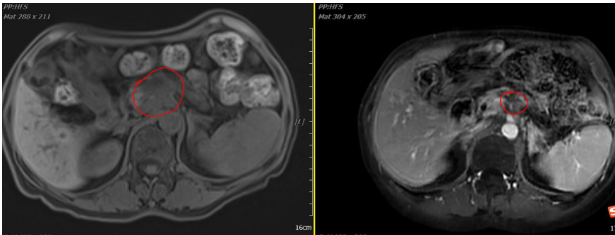

1)、病例展示一:胰体恶性肿瘤

胰体部恶性肿瘤(5.1*4.1cm),病灶包绕门静脉主干、腹腔干、肠系膜上动脉,腹腔干受压变窄,致门静脉、脾静脉闭塞伴侧枝循环形成,伴门静脉左侧、腹膜后淋巴结转移。病理诊断(病理E2025-00115):腺癌。治疗方案:碳离子放疗(2025-06-12)总剂量:PTV:55.2Gy(RBE)/12Fx。同步化疗:吉西他滨单药,第1、8、15天 Q4W。

影像学对比

2025-05-30 2025-10-16